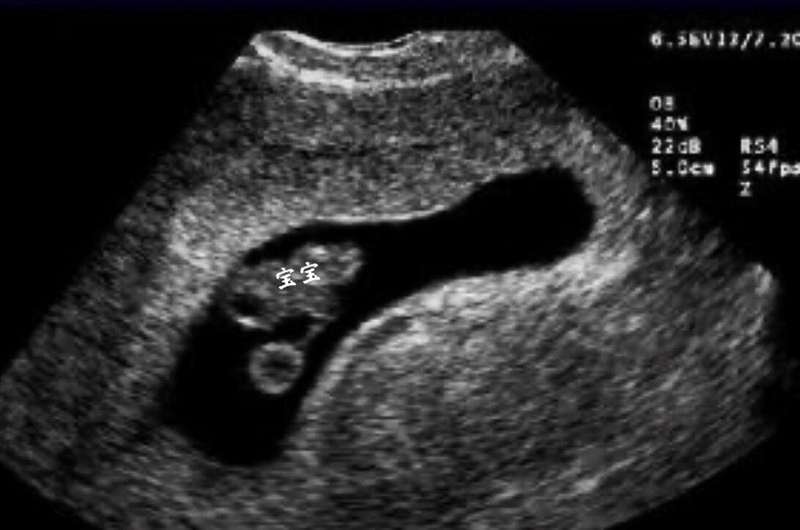

作者:李品 陳萍 整個(gè)孕期,孕媽媽需要幾次超聲檢查呢?經(jīng)常做會(huì)影響寶寶健康嗎?今天來(lái)細(xì)數(shù)一下幾次必須要做的超聲檢查。 第一次超聲檢查:孕6-9周期間,主要觀察是否為宮內(nèi)妊娠,排除宮外孕,排除滋養(yǎng)細(xì)胞疾病等,是否有胚芽,是否有原始胎心搏動(dòng)。判斷是單胎還是多胎,多胎要判斷是哪一種多胎,通俗說(shuō)就是一個(gè)受精卵發(fā)出來(lái)的多胎還是多個(gè)受精卵長(zhǎng)出來(lái)的,專業(yè)上說(shuō)就是:胎兒的絨毛膜性。還要觀察盆腔環(huán)境,有無(wú)子宮肌瘤和卵巢囊腫。 注意事項(xiàng):陰道超聲需要排空小便;腹部超聲需要憋尿。 第二次超聲檢查在孕11到孕13周6天之間,檢查主要內(nèi)容:測(cè)量NT,也就是胎兒頸后透明帶。通過NT數(shù)值,結(jié)合孕媽的年齡,血清學(xué)指標(biāo),綜合判斷胎兒唐氏綜合征的風(fēng)險(xiǎn)。除了測(cè)量NT,在這次超聲時(shí),可以大致進(jìn)行胎兒一些結(jié)構(gòu)的觀察,如有無(wú)頭顱,有無(wú)缺少一側(cè)肢體,有無(wú)大的臍膨出等,可以更早期的排除一些嚴(yán)重影響胎兒的結(jié)構(gòu)畸形如:無(wú)腦兒等。但是更加詳細(xì)的結(jié)構(gòu)觀察還是要到中孕期的系統(tǒng)篩查,也就是俗稱的大排畸。 注意事項(xiàng):無(wú)需憋尿,如果胎兒姿勢(shì)不合適不容易檢查,可以輕輕撫摸肚子或者走動(dòng)走動(dòng)讓胎兒調(diào)整姿勢(shì)以便檢查。 值得大家期待的是,在我們一婦嬰檢查NT超聲,您的報(bào)告上都會(huì)有一張圖2所示的寶寶的照片哦。 第三次超聲檢查孕20-24周,檢查項(xiàng)目:產(chǎn)前診斷三級(jí)篩查,俗稱大畸形篩查,也叫大排畸。主要為檢查胎兒是否患有重大結(jié)構(gòu)畸形,可以排除胎兒大的結(jié)構(gòu)畸形,如無(wú)腦兒、腦膨出、胸腹壁缺損內(nèi)臟外翻、單心腔、致死性軟骨發(fā)育不良、嚴(yán)重的脊柱裂等。耗時(shí)較長(zhǎng),當(dāng)胎兒體位不佳時(shí),需要適當(dāng)走動(dòng)再次檢查。 注意事項(xiàng):三維、四維不是產(chǎn)前III級(jí)篩查必須檢查。我們的大排畸超聲,不是用三維四維來(lái)進(jìn)行診斷和觀察的,就像照相館,你可以看到你認(rèn)識(shí)的照片,但是攝影師不會(huì)也不可能告訴你,照片中的人是否得病了一樣,三維是給您能看得懂的表面照片,不能穿透性的看到胎兒內(nèi)部結(jié)構(gòu)。所以,您在做排畸的時(shí)候,屏幕上顯示的圖(比如圖3,就是排畸時(shí)候的胎兒頭顱的圖像),可能您都看不懂。 另外,不是所有的畸形都能通過大排畸得到診斷,這個(gè)可以通過我們的告知書來(lái)詳細(xì)了解。有疑問可以上好大夫網(wǎng)站找我們進(jìn)行咨詢。 第四次超聲檢查孕28-32周,檢查項(xiàng)目:胎兒生長(zhǎng)發(fā)育檢測(cè)。到了孕28-32周,孕媽媽需要再次進(jìn)行超聲檢查,測(cè)量胎兒雙頂徑、頭圍、腹圍、股骨長(zhǎng)度等,評(píng)估胎兒的生長(zhǎng)發(fā)育情況是否符合孕周,也可觀察孕晚期進(jìn)展的明顯的結(jié)構(gòu)畸形。還可以評(píng)估羊水量和胎盤,臍帶血流情況。 注意事項(xiàng):這次檢查不是胎兒結(jié)構(gòu)畸形篩查。 第五次超聲檢查孕35-38周及分娩前,檢查項(xiàng)目:胎兒生長(zhǎng)發(fā)育檢測(cè)。檢查胎兒胎位、雙頂徑、頭圍、腹圍、股骨長(zhǎng)、胎盤、羊水、臍血流指數(shù)等情況,估算胎兒的體重,了解羊水多少,檢查胎盤的位置,為臨床醫(yī)師提供分娩技術(shù)指標(biāo)。 我可以多做幾次超聲看寶寶嗎?超聲是一種聲波傳導(dǎo),不存在電離輻射和電磁輻射,這種聲波對(duì)寶寶健康沒有危害的。在高齡產(chǎn)婦、妊娠期糖尿病、妊娠期高血壓孕媽媽等特殊情況,需要增加超聲檢查次數(shù)檢測(cè)胎兒情況,不會(huì)影響胎兒的生長(zhǎng)發(fā)育。當(dāng)然孕媽媽還是要在有臨床指征的情況下做超聲檢查,沒有必要經(jīng)常跑醫(yī)院增加焦慮情緒。